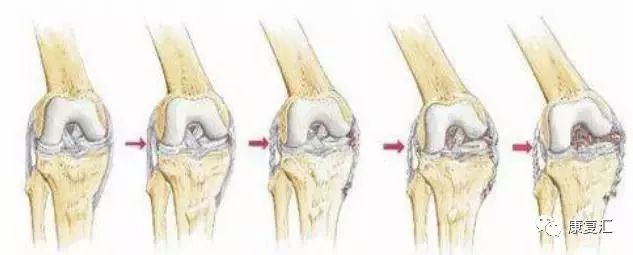

特发性骨坏死

较高龄者 (>55岁),大部分无诱因,突然发生膝关节剧痛,夜间痛明显,关节内注射糖皮质激素无效,股骨髁关节面上有压痛,活动度影响不显著。X线摄片显示股骨内髁骨缺损及透亮层。